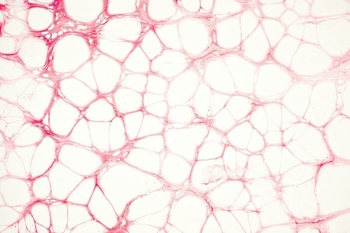

At present, about 20% of couples in the Czech Republic are infertile, and this number is growing every year. A couple is...